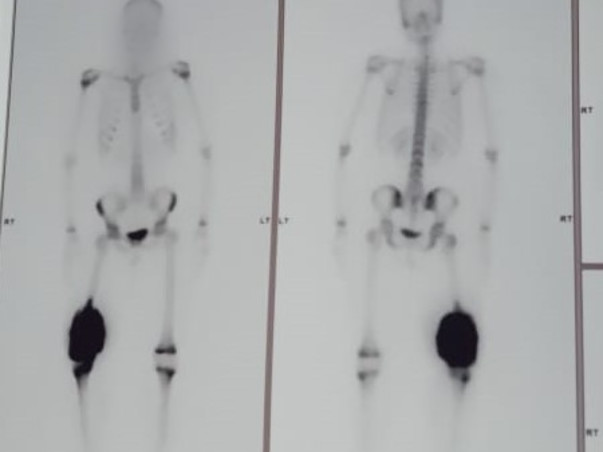

Saheetha is suffering from Bone cancer, A couple of months ago Sahitha's leg was swollen because she fell down while playing at home, we used some local medicine to cure her swollen leg but as the days passed on the condition of swollen leg increased so we approached hospital in Kakinada, doctors declared that it's BONE CANCER and asked us to go Homi Bhaba cancer hospital in Vizag for further treatment.

Firstly, Doctor's said removing the leg is the only solution, after a couple of days doctors came up with another option to replace the damaged part of the bone with artificial bone if possible after analyzing the level of seriousness after doing surgery, This surgery is going to be done in Bombay.